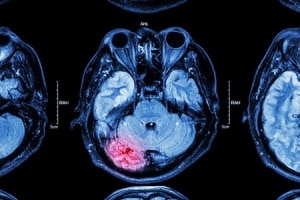

Understanding CTE in NFL Concussion Cases

*Photo Credit – Ann C McKee, MD, VA Boston/Boston University School of Medicine.